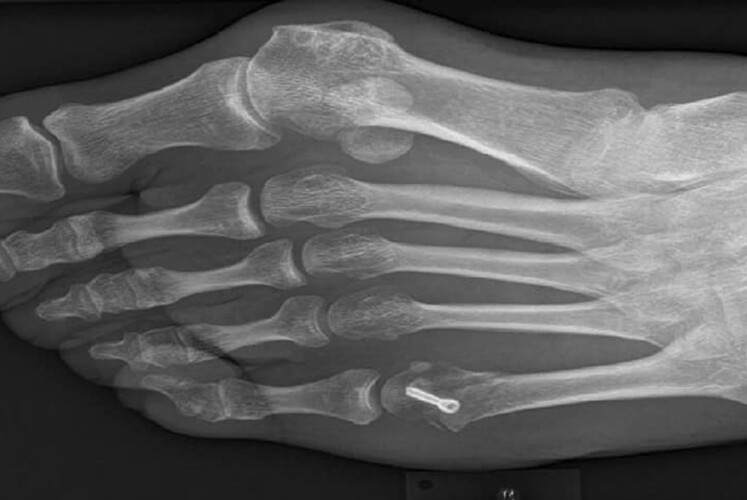

Ein bekannter Biathlet schrieb vor kurzem auf seiner Facebook-Seite: „Seit einigen Jahren habe ich mit starken Fußschmerzen zu kämpfen. Ich hatte einen Hallux valgus, ein Schiefstehen des Großzehs. Es wurde immer schmerzhafter und konservative Methoden brachten mich nicht mehr weiter. Ich habe mich diesen Frühling dazu entschieden, den Fuß zu operieren und musste nach der OP im April eine Sportpause von 6 Wochen einlegen. Seit einigen Wochen bin ich nun mit viel weniger Schmerzen zurück im Training.“

Bereits 2018 hatten wir die biomechanischen Zusammenhänge zwischen Gehen und Gleiten untersucht. Die Ergebnisse hatten wir in GLIDING 2(2019) veröffentlicht. Als experimentelle Plattform diente eine hochauflösende Druckmessplatte. Mit zusätzlichen Videoanalysen konnte ein ganzheitliches Bild der biomechanischen Vorgänge erhalten werden. Der Versuchsablauf wurde durch eine Ganganalyse eingeleitet. Der Athlet, der damals schon an einem auffälligen Hallux valgus am linken Fuß litt, zeigte ein entsprechendes Gangbild, das durch signifikante Unterschiede in der Druckverteilung zwischen linkem und rechtem Fuß gekennzeichnet war. Insbesondere der Erstkontakt zwischen Fuß und Druckmessplatte erfolgte schmerzvermeidend, obwohl dies vom ihm nicht beabsichtigt war. Interessanterweise wurden ähnliche Muster beim Gleiten mit Skiern über die Platte erhalten. Die Druckverteilung zeigte eine geringere Intensität unter dem linken Ski und es lässt sich daraus schließen, dass durch die unterschiedlich wirkenden Kräfte auch die Tribologie beeinflusst wird. Kraftunterschiede zwischen linkem und rechtem Ski werden von unterschiedlichen Reibungskräften begleitet. Als Konsequenz erfährt der Athlet eine Verdrehung entlang der vertikalen Körperachse, was sich nachteilig auf die Vortriebskraft beim Doppelstockfahren auswirkt.